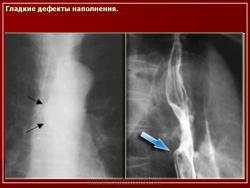

ПС. Пищевод. Набор изображений № 2. Новообразования пищевода. Варикозно расширенные вены пищевода. +

Пищевод.  Набор изображений № 2.